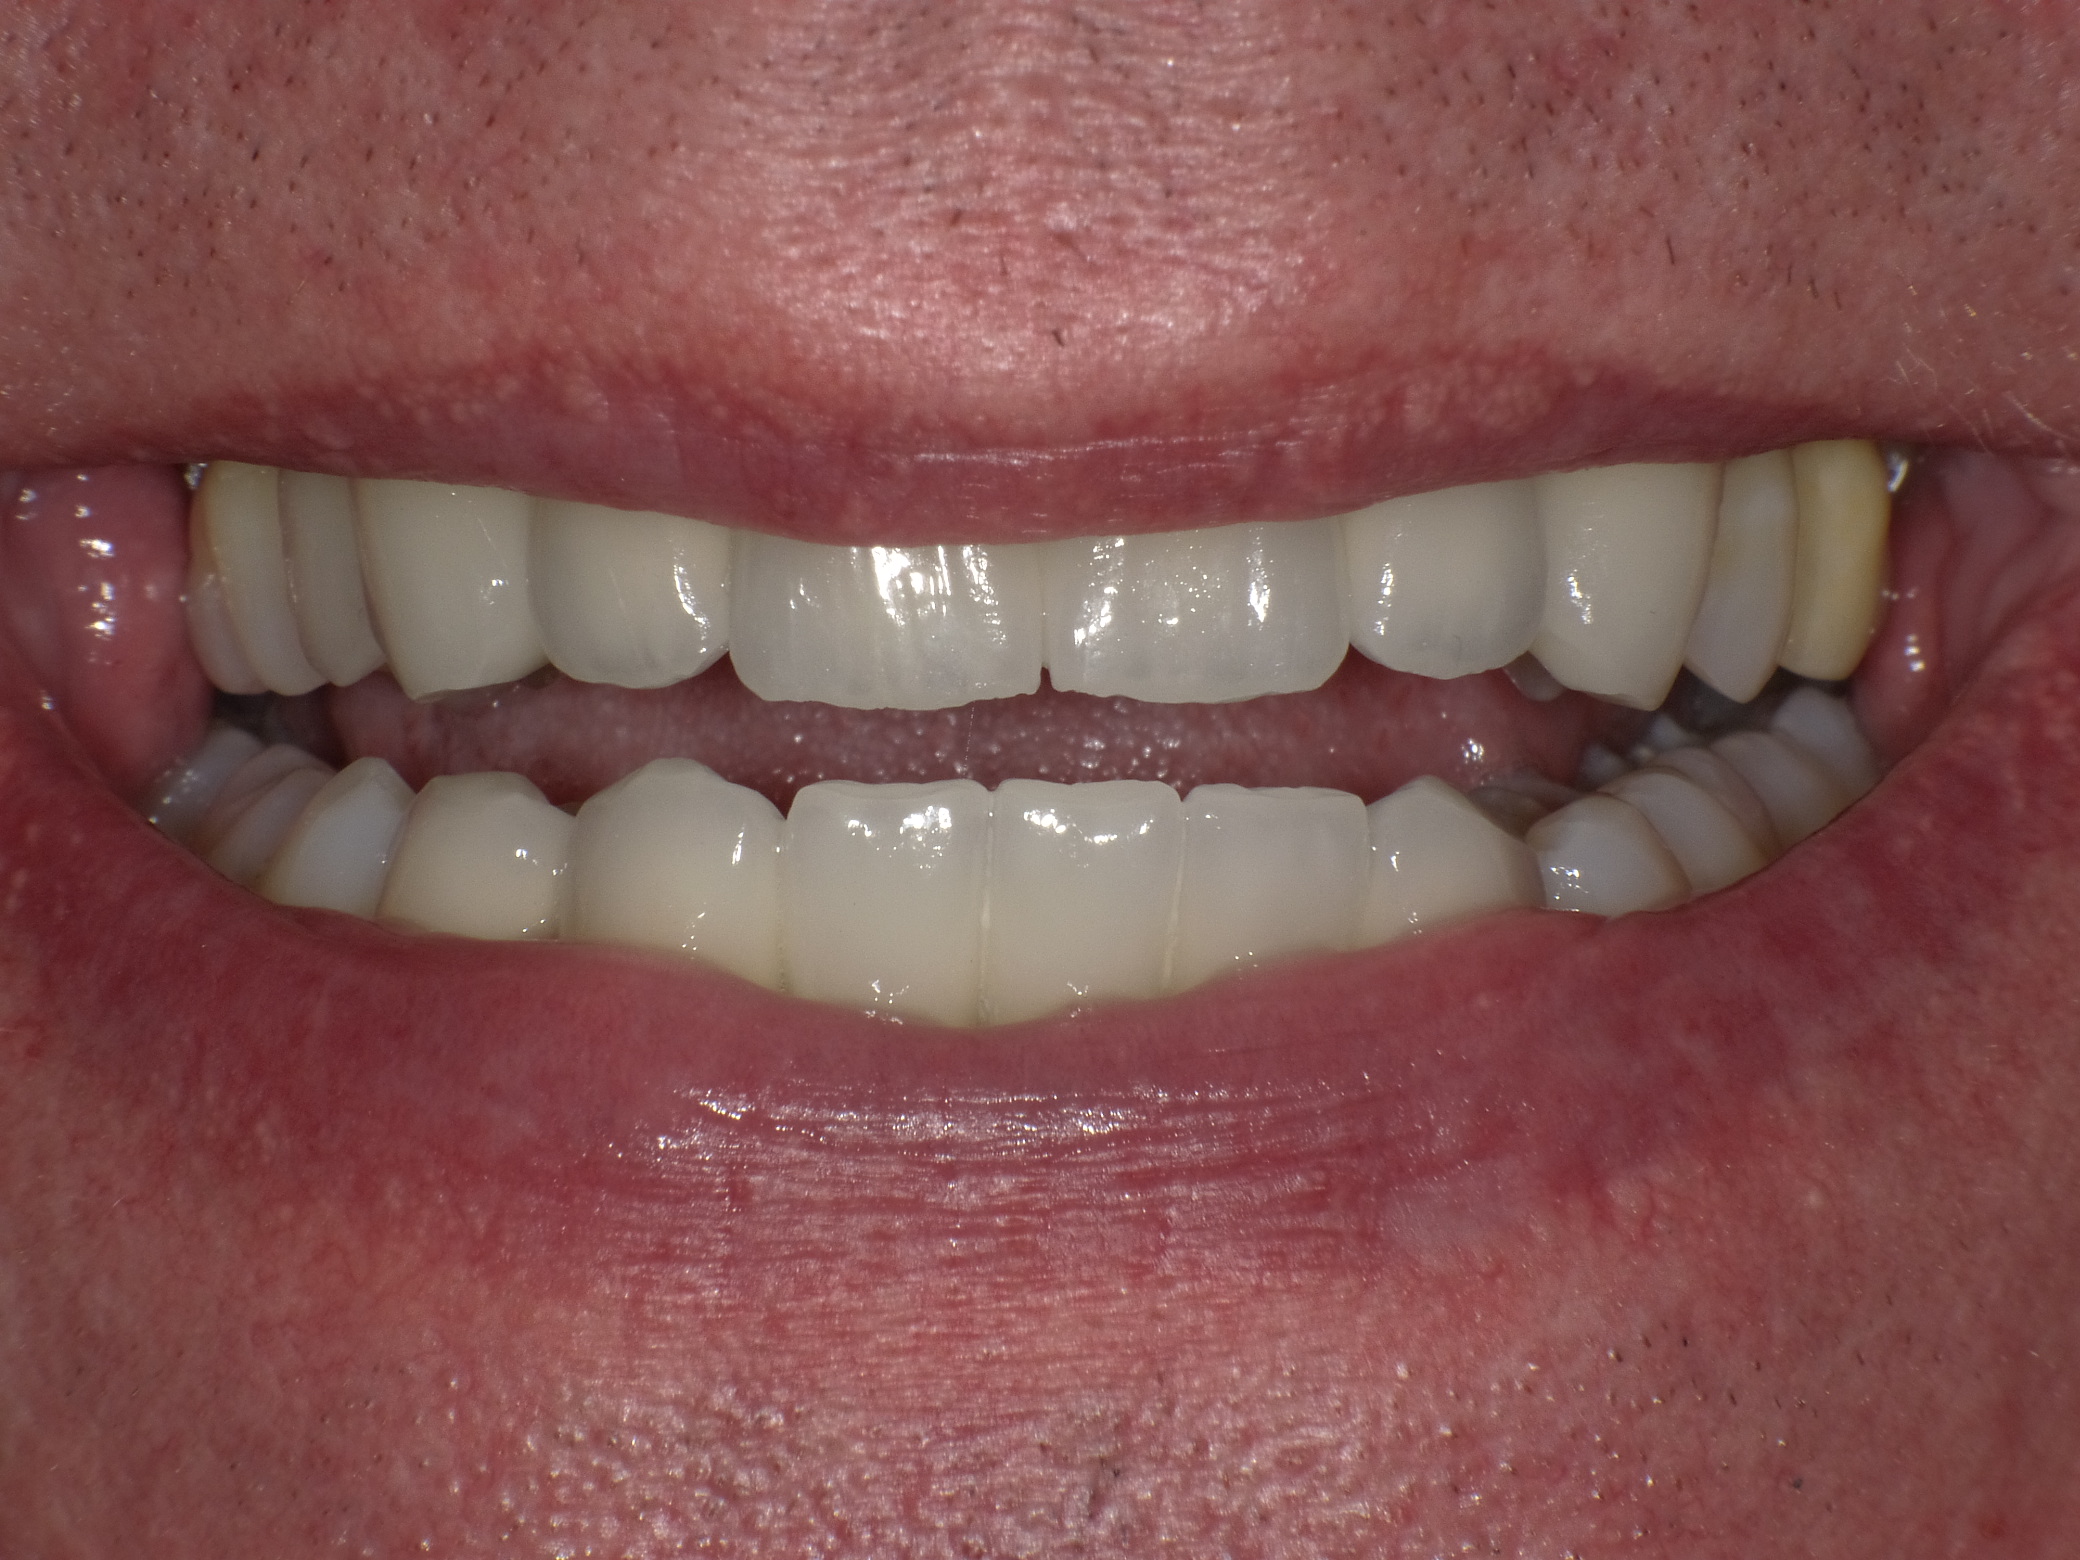

Diverse Vorbehandlungen mit für die Patientin absolut inakzeptablem Ergebnis

Vorher: Diverse Vorbehandlungen mit für die Patientin absolut inakzeptablem Ergebnis

Komplette Veränderung mit vollkeramischen Kronen und Veneers in nur 2 Langzeitterminen; auch hier nachher ganz anderes Auftreten der Patientin, die ihre Zähne jetzt gerne zeigt und wieder gerne lacht

Nachher: Komplette Veränderung mit vollkeramischen Kronen und Veneers in nur 2 Langzeitterminen; auch hier nachher ganz anderes Auftreten der Patientin, die ihre Zähne jetzt gerne zeigt und wieder gerne lacht